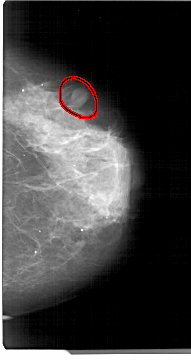

A_1305_1.LEFT_MLO

LEFT_MLO LINES 5491 PIXELS_PER_LINE 3211 BITS_PER_PIXEL 12 RESOLUTION 43.5 NON_OVERLAY

FILE: A_1305_1.RIGHT_MLO.OVERLAY

TOTAL_ABNORMALITIES 1

ABNORMALITY 1

LESION_TYPE MASS SHAPE OVAL MARGINS CIRCUMSCRIBED

ASSESSMENT 4

SUBTLETY 4

PATHOLOGY BENIGN

TOTAL_OUTLINES 1

BOUNDARY